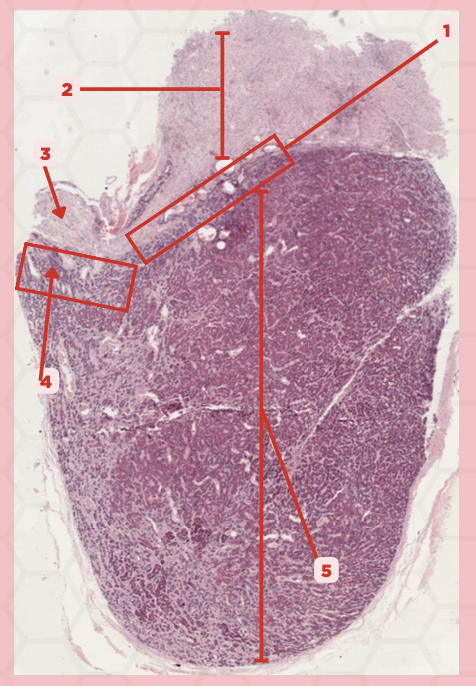

Adenohypophysis

What does #1, #4, and #5 form?

Pituitary

Identify the specimen.

Intermediate Lobe

Identify the structure labeled as 1.

Posterior Lobe

Identify the structure labeled as 2.

Pituitary Stalk

Identify the structure labeled as 3.

Pars Tuberalis

Identify the structure labeled as 4.

Anterior Lobe

Identify the structure labeled as 5.

Neural Ectoderm

What ectoderm is #2  derived from?

Oral Ectoderm

What ectoderm #1, #3, & #4 derived from?